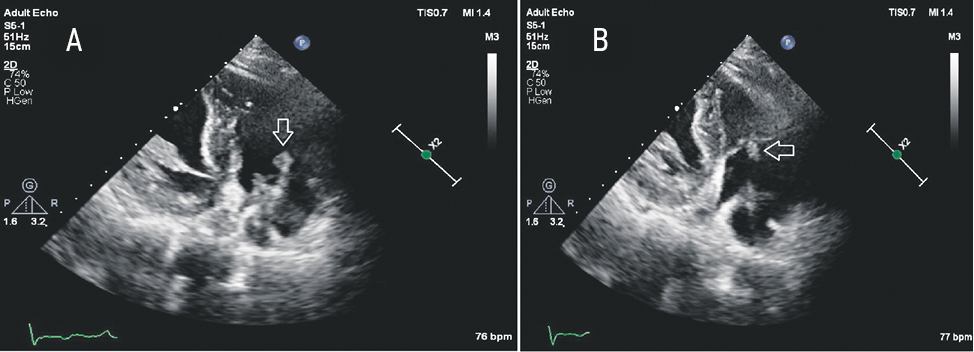

In March 2019, fever and night sweats resumed, and therefore the patient was hospitalized with a diagnosis of ARVI, acute bronchitis. In laboratory data, leukocytosis, a twofold increase in ESR, and a 12-fold excess of CRP were noted. Blood cultures were not performed. Lung x-ray showed no pathology. Within 17 days the patient received the following treatment: ceftriaxone 2 g, levofloxacin 500 mg, metronidazole 500 mg. By the time of discharge, the clinical condition and laboratory readings had returned to normal. For the next 4 months after the discharge, the patient felt well. However, in mid-July 2019, fever and bouts of night sweats resumed. By the beginning of August 2019, shortness of breath again joined the general symptoms of inflammation, and therefore the patient was again hospitalized. In laboratory tests, leukocytosis, a 55-fold increase in CRP, and mild anemia were present. Staphylococcus epidermidis was isolated from blood cultures. Orthopantomogram revealed signs of chronic periodontitis 26, 43, 47 teeth. Contrast multispiral CT of the lungs revealed embolic, destructive left-sided lower lobe pneumonia complicated by abscess, as well as multiple PE (segmental branches) on both sides. The finding with transthoracic echocardiography was initially regarded as a vegetation in the projection of the TV, although later, with TEE, classical vegetations on the atrial and ventricular paceaker electrodes were reliably identified (Fig. 5), as well as local uneven thickening and echogenicity of the electrode fragments, regarded as ‘sleeve’ type vegetation (Fig. 6). There were no reliable signs of TV damage.

Fig. 5. Echocardiography of patient B. Loose vegetation, fixed on the ventricular electrode near the tricuspid valve. Modified three-chambered apical section: A — Diastole, tricuspid valve open; B — Systole, tricuspid valve closed. Formation is fixed to the electrode; the cusps of the own tricuspid valve appear intact.

Fig. 6. EchoCG of patient B. Modified 3-chamber apical section. Uneven thickening and echogenicity of the area of the ventricular electrode located above the cusps of the tricuspid valve. This picture was regarded as a probable vegetation of the “sleeve” type.